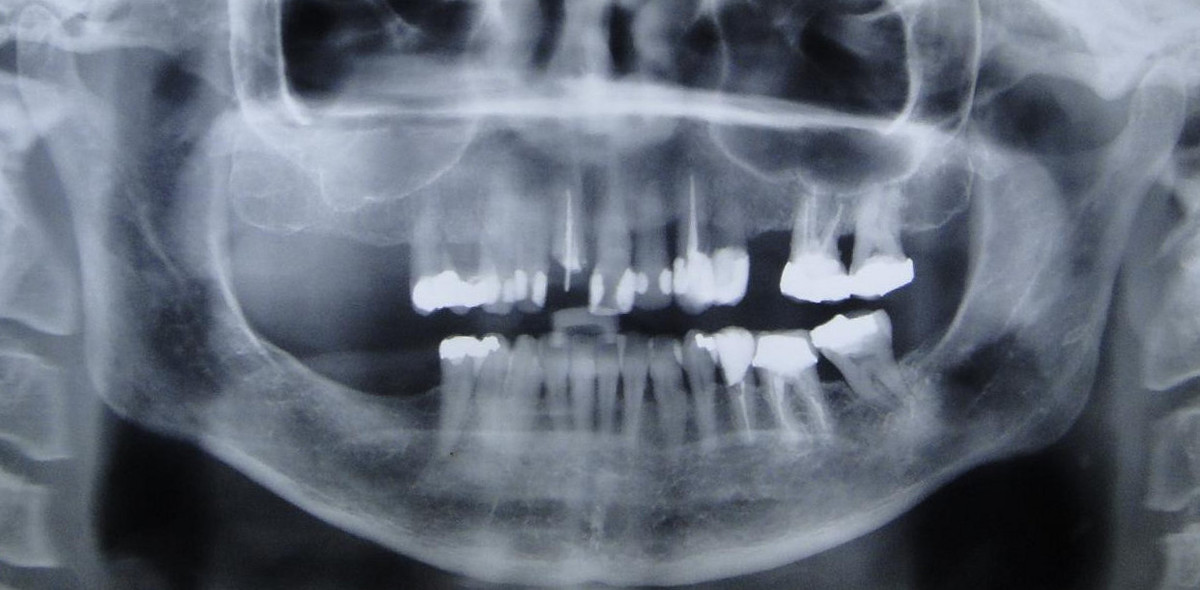

PRÓTESE TOTAL FIXA EM IMPLANTES

M.C.R.B.S.

S.O.P.

E.G.D.L.D.